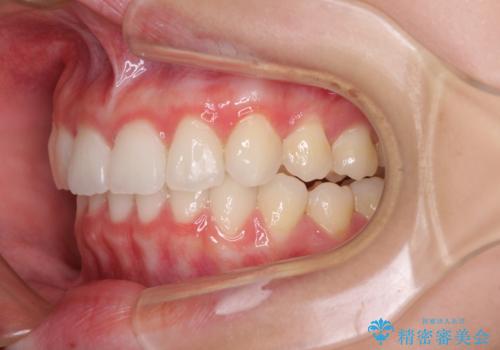

- 前歯2本が飛び出してることを気にして来院された患者様です。

全体的に黄ばんだ歯の色も気になるとのことで、マウスピース矯正により飛び出した前歯を治しつつ、ホームホワイトニングを併用して黄ばみを解消していくこととしました。

歯と歯の間を削ることで、飛び出した前歯が引っ込み、スッキリとした口元となりました。

歯の黄ばみも改善され、明るい歯並びとなりました。